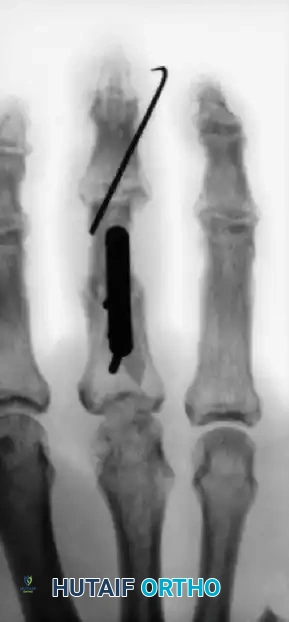

The following sequence illustrates the progression from injury to successful closed reduction and K-wire fixation into the trapezium:

Alternative pinning configurations for metacarpal shaft fractures: